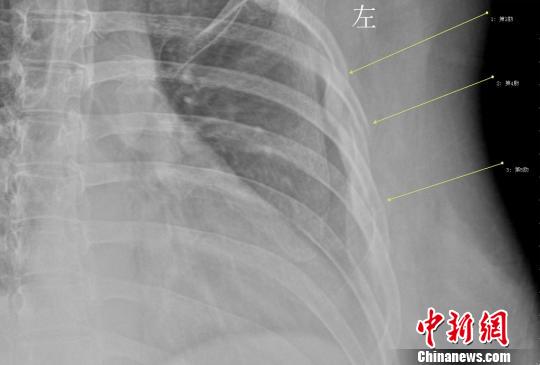

年輕女白領(lǐng)因咳嗽導(dǎo)致三根肋骨骨折 劉姍姍 攝

拍片結(jié)果顯示,她的第3、4、5肋骨骨折,胸外科醫(yī)生給她上了胸帶固定,并給予了止咳鎮(zhèn)痛的藥物治療。胸外科徐家行醫(yī)生詳細詢問病史,在排除了其他因素后,考慮還是咳嗽引起的肋骨骨折。